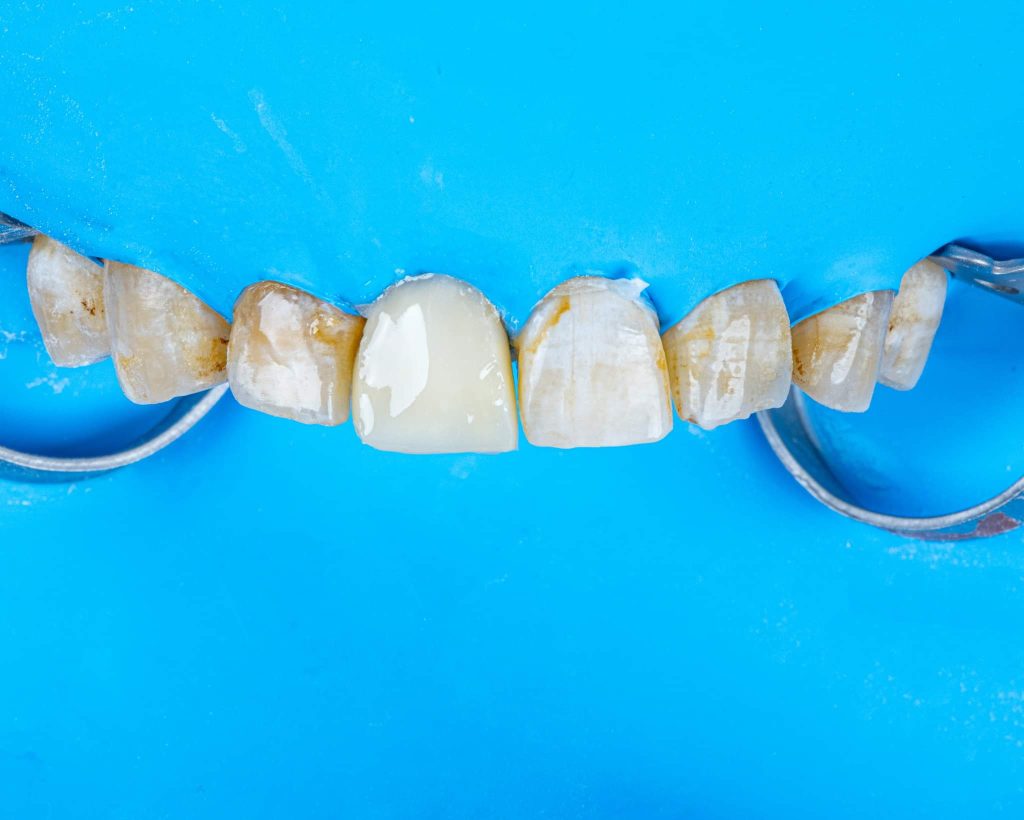

This is a case of discolored right central incisor for a 21 years-old-male patient. He had a history of previous trauma 2 years ago to his tooth and fracture, that was managed with a composite restoration. After clinical examination and x-ray imaging, the tooth was non-vital with periapical lesion.

After discussing the treatment options with the patient, he chose the direct composite veneer. The treatment included endodontic treatment, internal bleaching, direct composite veneer for the right central, and aesthetic reshaping for the laterals and left incisor also by composite restoration. The case completed in 2 sessions.